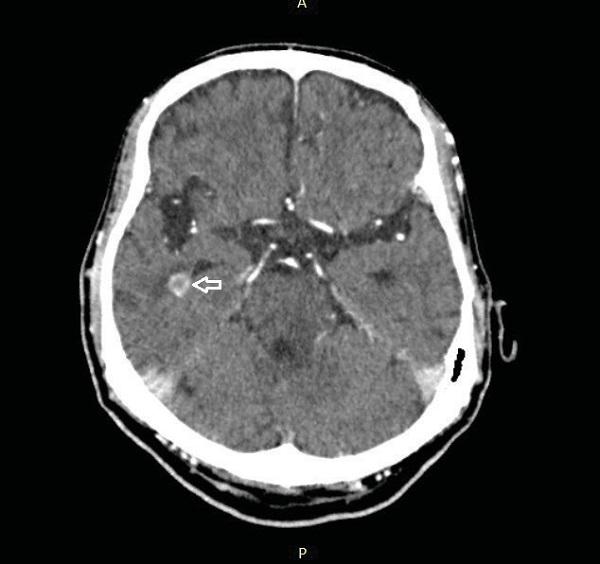

En la TC con contraste y en la RM, se observan lesiones intraparenquimatosas, únicas (15%) o múltiples (85%) (Figura 1)12. Estas varían en tamaño desde microscópicas (3-9 milímetros), hasta lesiones de varios centímetros13; además presentan centro hipodenso y bordes resaltados compatibles con realce en anillo; en ocasiones lesiones hiperdensas, con realce solido cuando son pequeñas (Figura 1). Se comportan como lesiones con efecto masa asociadas a edema vasogénico circundante12,13 y de manera característica, las formas parasitarias se localizan en la periferia de las lesiones14.

Sus localizaciones más frecuentes son los ganglios basales, regiones corticales y subcorticales de lóbulos temporal, frontal y parietal13. Tanto en la clínica como en la imagenología, la toxoplasmosis cerebral y el Linfoma tienen comportamiento similar, pero guardan algunas diferencias importantes (tabla 1).

El diagnóstico se basa en la biopsia cerebral. Esta técnica resulta costosa y restringida, razón por la cual se realiza la TC y la RM. En el caso de la TC simple las lesiones son isodensas o hiperdensas (92%), pero después de la administración de contraste manifiestan reborde hiperdenso con centro hipodenso no asociados a edema vasogénico compatible con el patrón de realce en anillo22 (Figura 1); en la RM adquiere un patrón de isointensidad o hipointensidad en T2, debido a la alta relación núcleo/ citoplasma de las células malignas 18. Es de tener en cuenta que la presencia de una lesión única, de gran tamaño (> 3 cm) y localizada a nivel de la sustancia blanca periventricular sugiere el diagnóstico de Linfoma12,16,23.

3. Estadio vesicular-coloidal: parásitos muertos que desencadenan reacción inflamatoria aguda. Se asocia a edema perilesional y la formación de una cápsula hipodensa. Con contraste se observa realce en anillo (Figura 1)